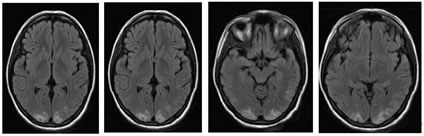

Figure 2: Posterior reversible encephalopathy syndrome (PRES) in a patient on chemotherapy for carcinoma right ovary who presented with one episode of seizure, BP was 150/100mm of Hg.MRI showed involvement of typical and atypical regions.Relatively symmetrical FLAIR cortical, subcortical edema extending to deep white matter of bilateral posterior parietal and occipital lobes, periventricular white matter,bilateral lentiform nuclei,right thalamus,bilateral cerebellar hemispheres, but no diffusion abnormalities (not shown)